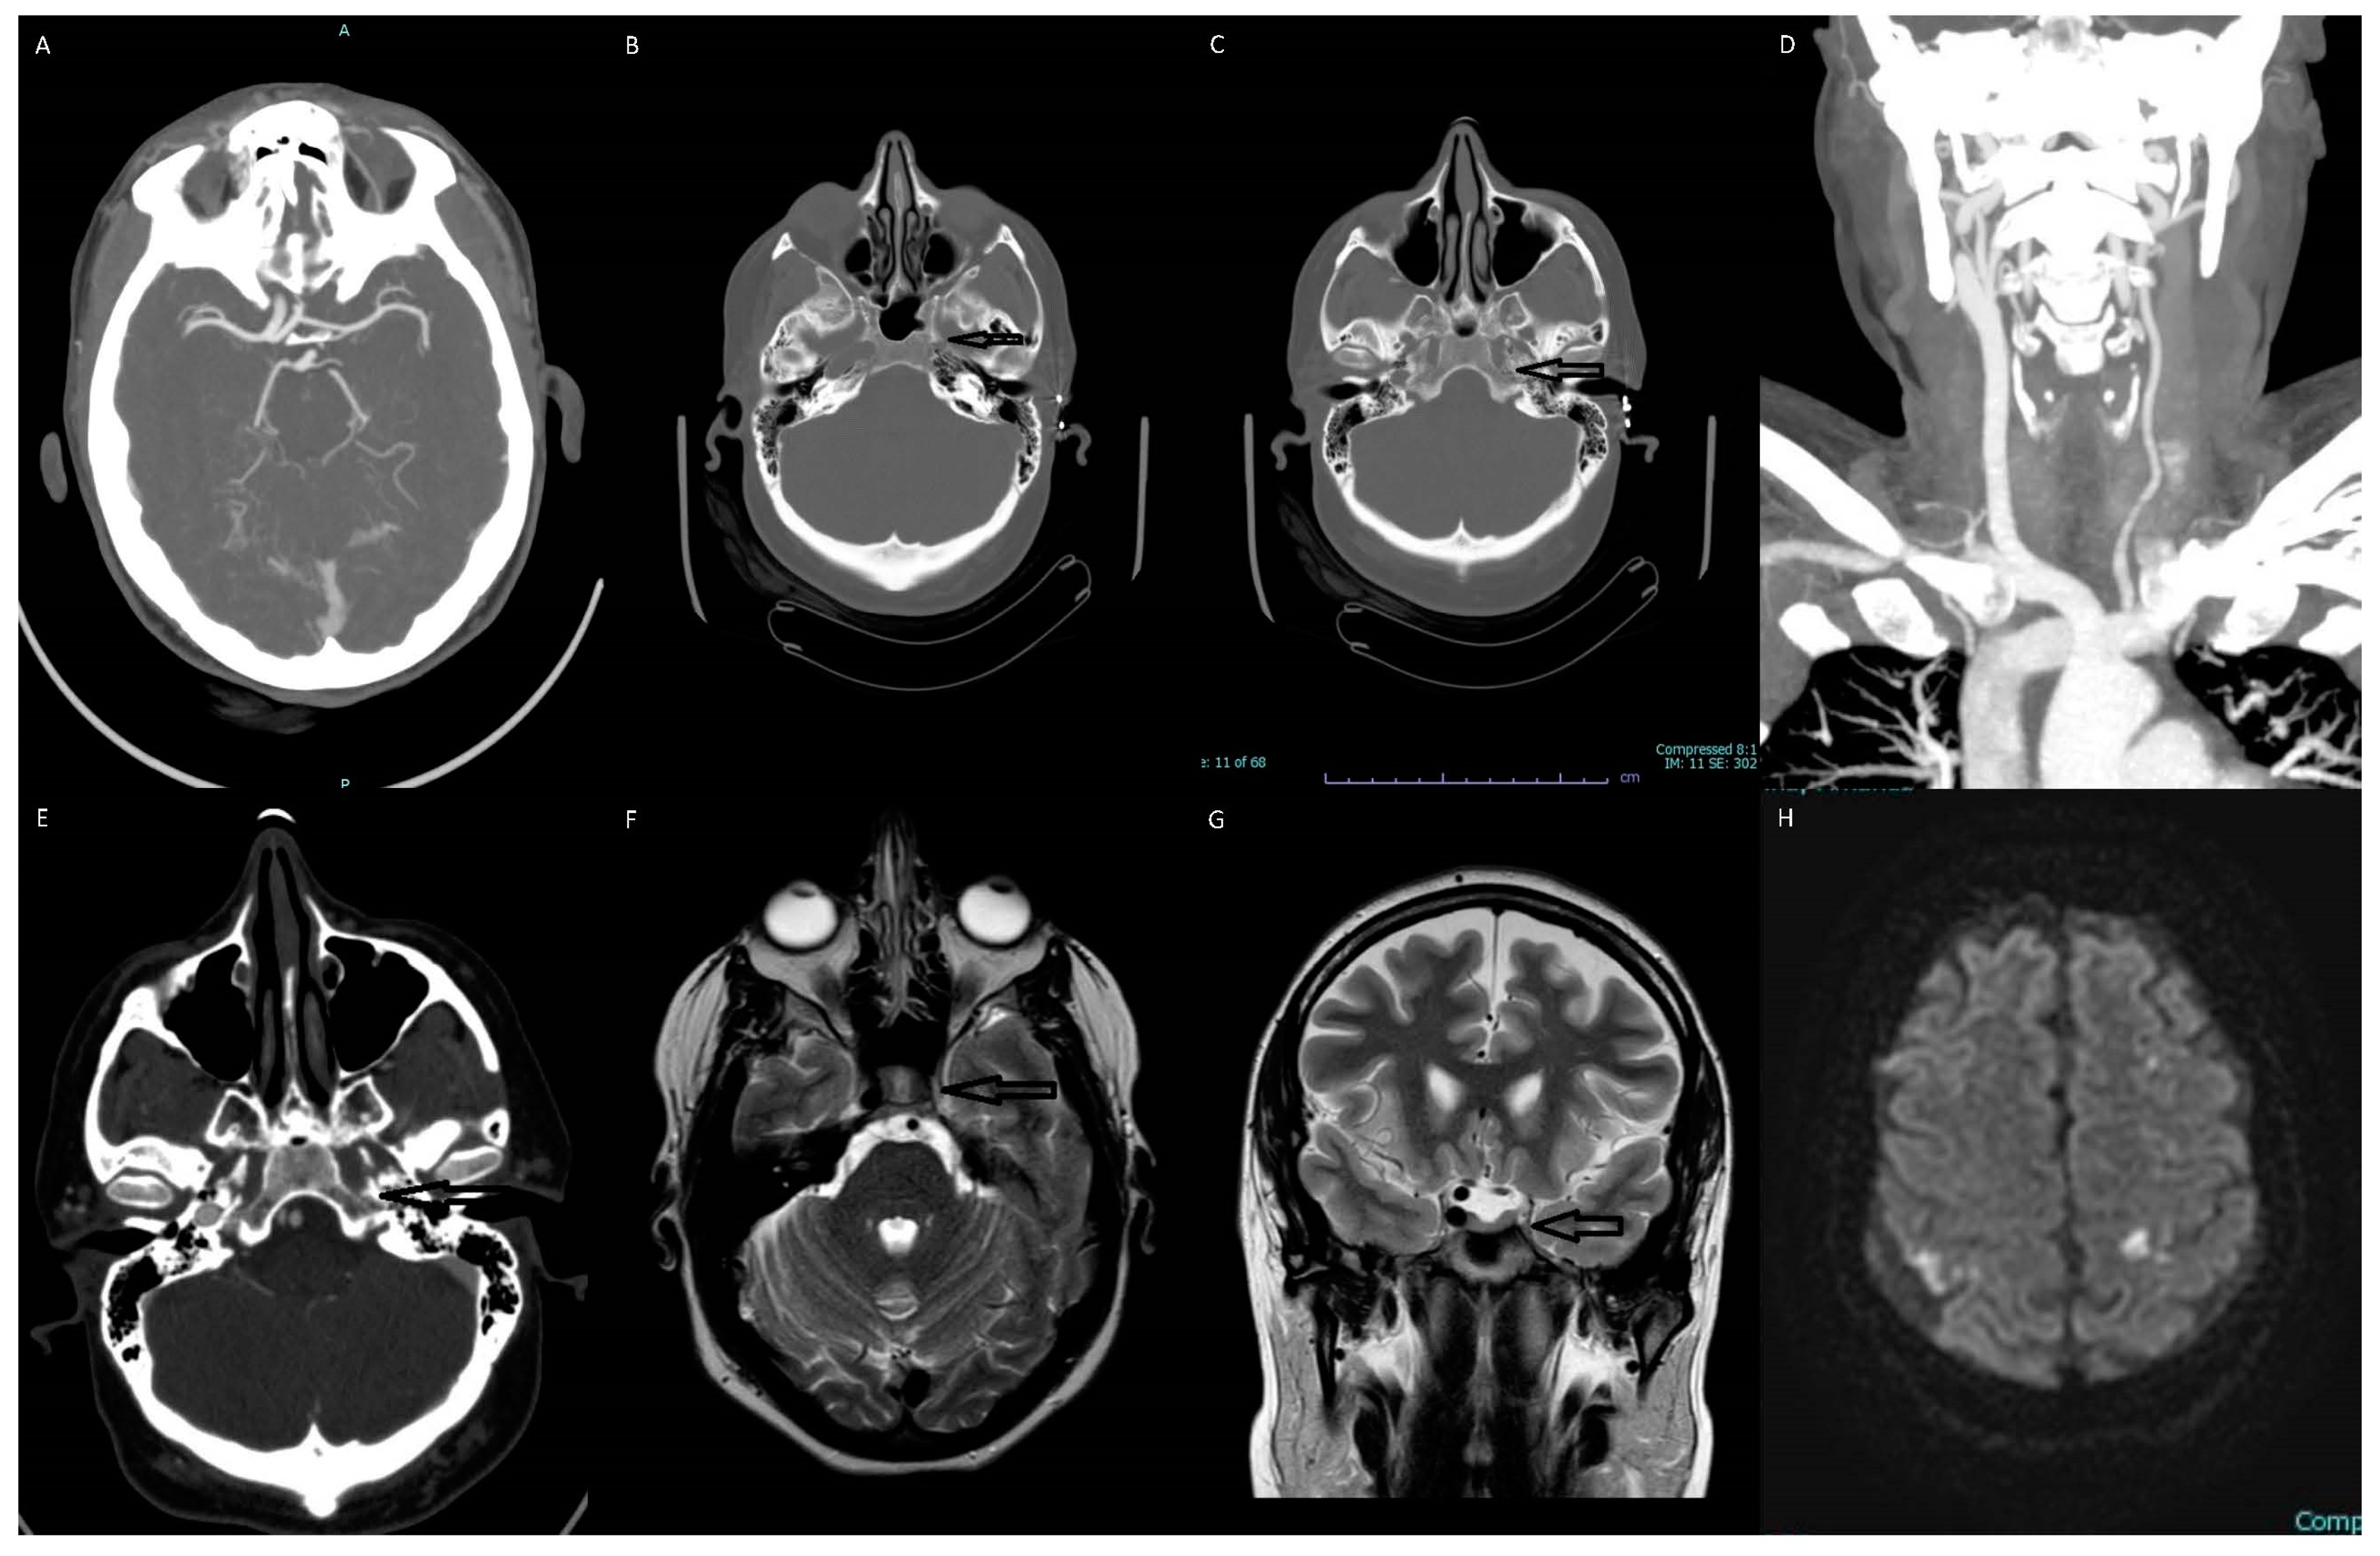

Figure 1. Multiple images depict the absence of the left internal carotid artery (ICA). (A) The transverse section of the CTA of the brain shows an absent supraclinoid segment of the ICA on the left side. The left anterior and middle cerebral arteries are reconstituted via the anterior communicating and posterior communicating arteries. (B) The axial section of the brain CT scan shows an absent horizontal petrous segment of ICA on the left side. (C) The axial section of the brain CT scan shows an absent vertical petrous segment of ICA on the left side. (D) Coronal MIP CTA showing arterial branching from the aortic arch and an absent left ICA. (E) The axial section of the CTA of the brain shows an absent vertical petrous segment of ICA on the left side. (F) The axial T2 weighted MR image shows absent flow void of left ICA. (G) The coronal T2 weighted MR image shows absent flow void of left ICA. (H) The brain MR diffusion-weighted imaging (DWI) showing focal regions of ischemia in bilateral cerebral hemispheres.

The most significant findings of the patient’s laboratory workup were an elevated troponin of 336 and a proBNP of 19,572. Her laboratory studies also demonstrated mild hypokalemia at 3.3, elevated BUN at 29, a creatinine of 1.47, a mildly elevated ALT of 53, and an INR of 1.18. Imaging studies included: Dx-Chest, Echocardiogram, MR-Brain-W/O, MRV Head, CT-CTA Neck with and W/O, CT-CTA head with and W/O. The patient’s echo showed severely reduced left ventricular systolic function with an ejection fraction of 30%, apical akinesis, and a thrombus present in the left ventricular apex. Brain magnetic resonance imaging showed tiny multifocal areas of acute infarcts in the bilateral frontal, parietal, and left occipital lobes in the watershed distribution. There was no visualization of the flow of the intracranial left internal carotid artery. The follow-up CTA of the head and neck showed a congenital absence of the left internal carotid artery with no evidence of arterial dissection, occlusion, or aneurysm.